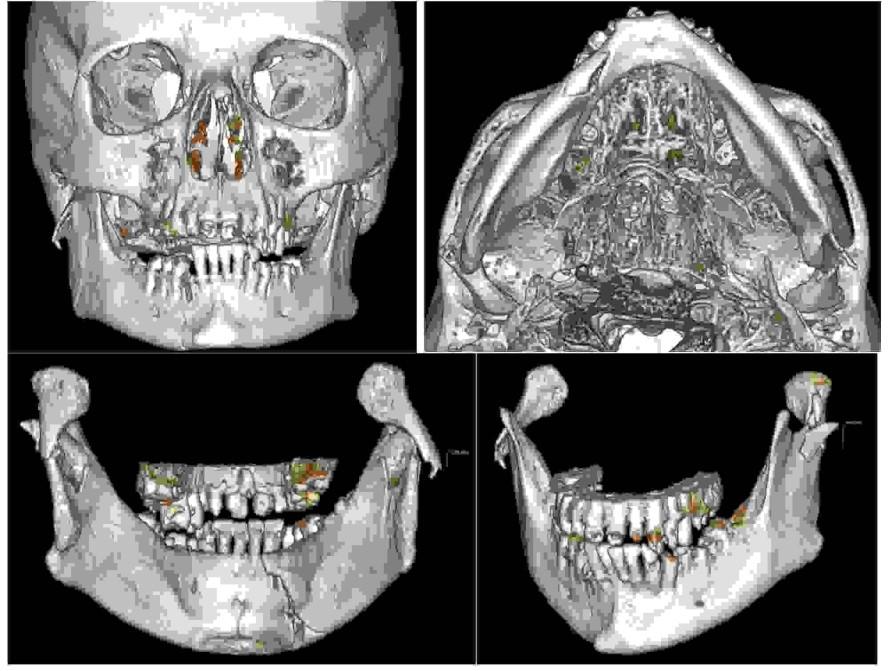

Korektę dysproporcji wielkości szczęki żuchwy można przeprowadzić na wiele sposobów uzależnionych od danej wady rozwojowej. Na podstawie poniższego zdjęcia pantomograficznego wskaż, jaki chirurgiczny zabieg ortognatyczny został wykonany:

Pytanie 72